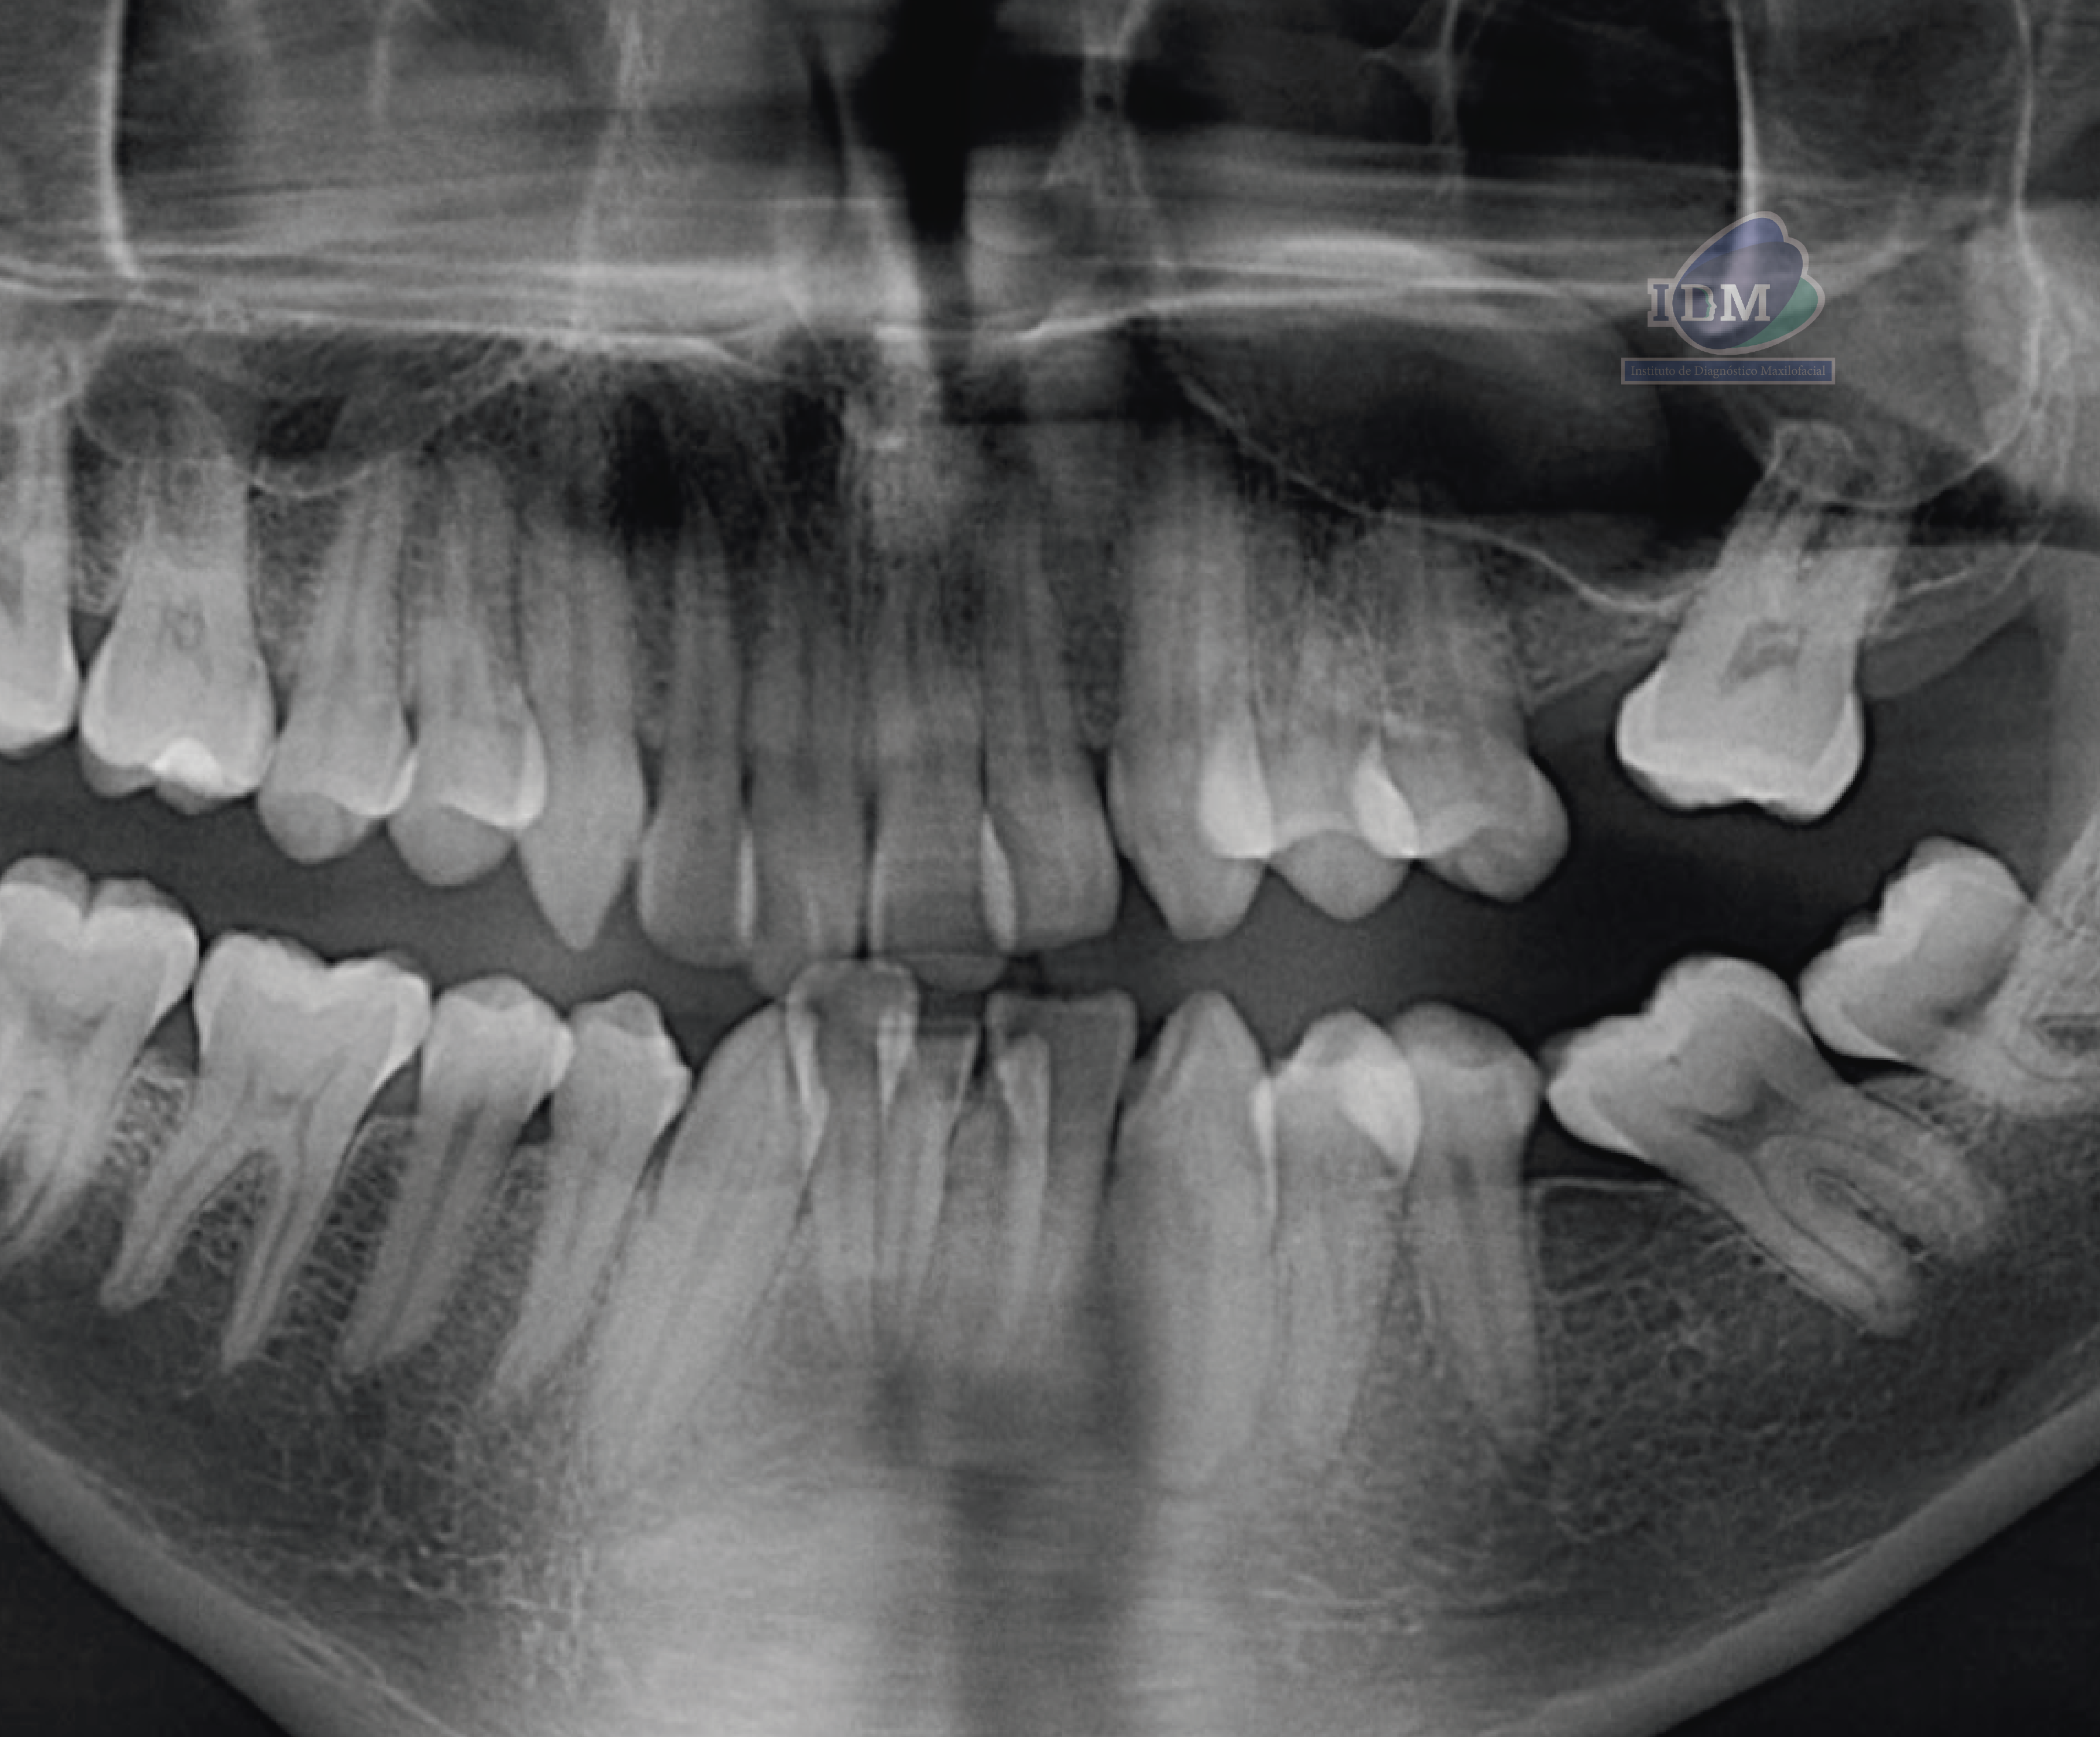

Radiografia Panorámica

A la evaluación de la radiografía panorámica se observa aplanamiento del contorno condilar bilateral, neumatización de ambos senos maxilares, la presencia de un quiste de retención mucoso en el seno maxilar izquierdo, asimismo también se observa apiñamiento dental, presencia de placa cervical mineralizada y la pieza 48 impactada hacia mesial.